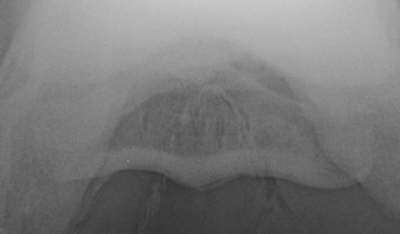

Skyline Röntgenaufnahme

Sklerosierung  und Aufhellungslinie in der Gleitfläche für die tiefe Beugesehne